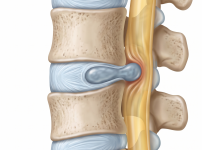

요추 추간판 탈출증 (허리디스크) | 서울건우 I 질환정보 (lumbar herniated intervert…

정의추간판 탈출증은 척추뼈 사이에서 완충 작용을 하는 추간판(디스크)이 돌출되거나 파열되어 주변 신경을 자극하는 질환입니다. 흔히 허리디스크라고 불리며, 신경이 눌리는 …